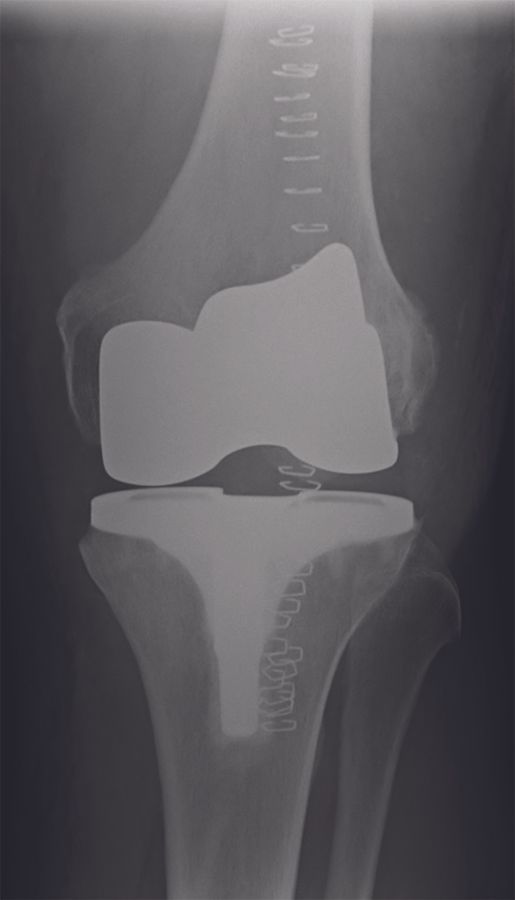

These new techniques represent an ongoing controversy, and there is currently no evidence that any of them lead to superior clinical outcome and long-term implant survival when compared to the classical MA technique. Nevertheless, there is a growing interest for these new techniques, since many surgeons believe that the classical MA concept is responsible for the 20% dissatisfaction rate in TKA. In this paper, we describe our preferred surgical technique for the adjusted MA philosophy using a modified extension gap first technique with less soft tissue releases and a guided-motion total knee design (Journey II BCS system, Smith & Nephew, Memphis, TN) (Figure 1).

Approximately 600 patients were operated in our clinic with the balanced gap technique presented in this paper. In this patient cohort, the HKA changed from -6.7° ± 3.6° (range, -0.5 to -19°) preoperatively to -2.9° ± 2.1° (range, -0.5 to -5.5°) postoperatively. Hence, a residual varus was seen in all patients (Figures 15 - 16).